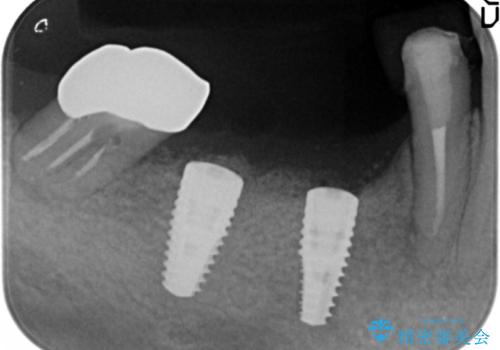

精査したところ、右下4の根尖病変及び右下5の欠損を認め、右下6は残根となり保存不可能な状態でした。

保存不可能な歯を抜去後、インプラント治療と根管治療を行いました。